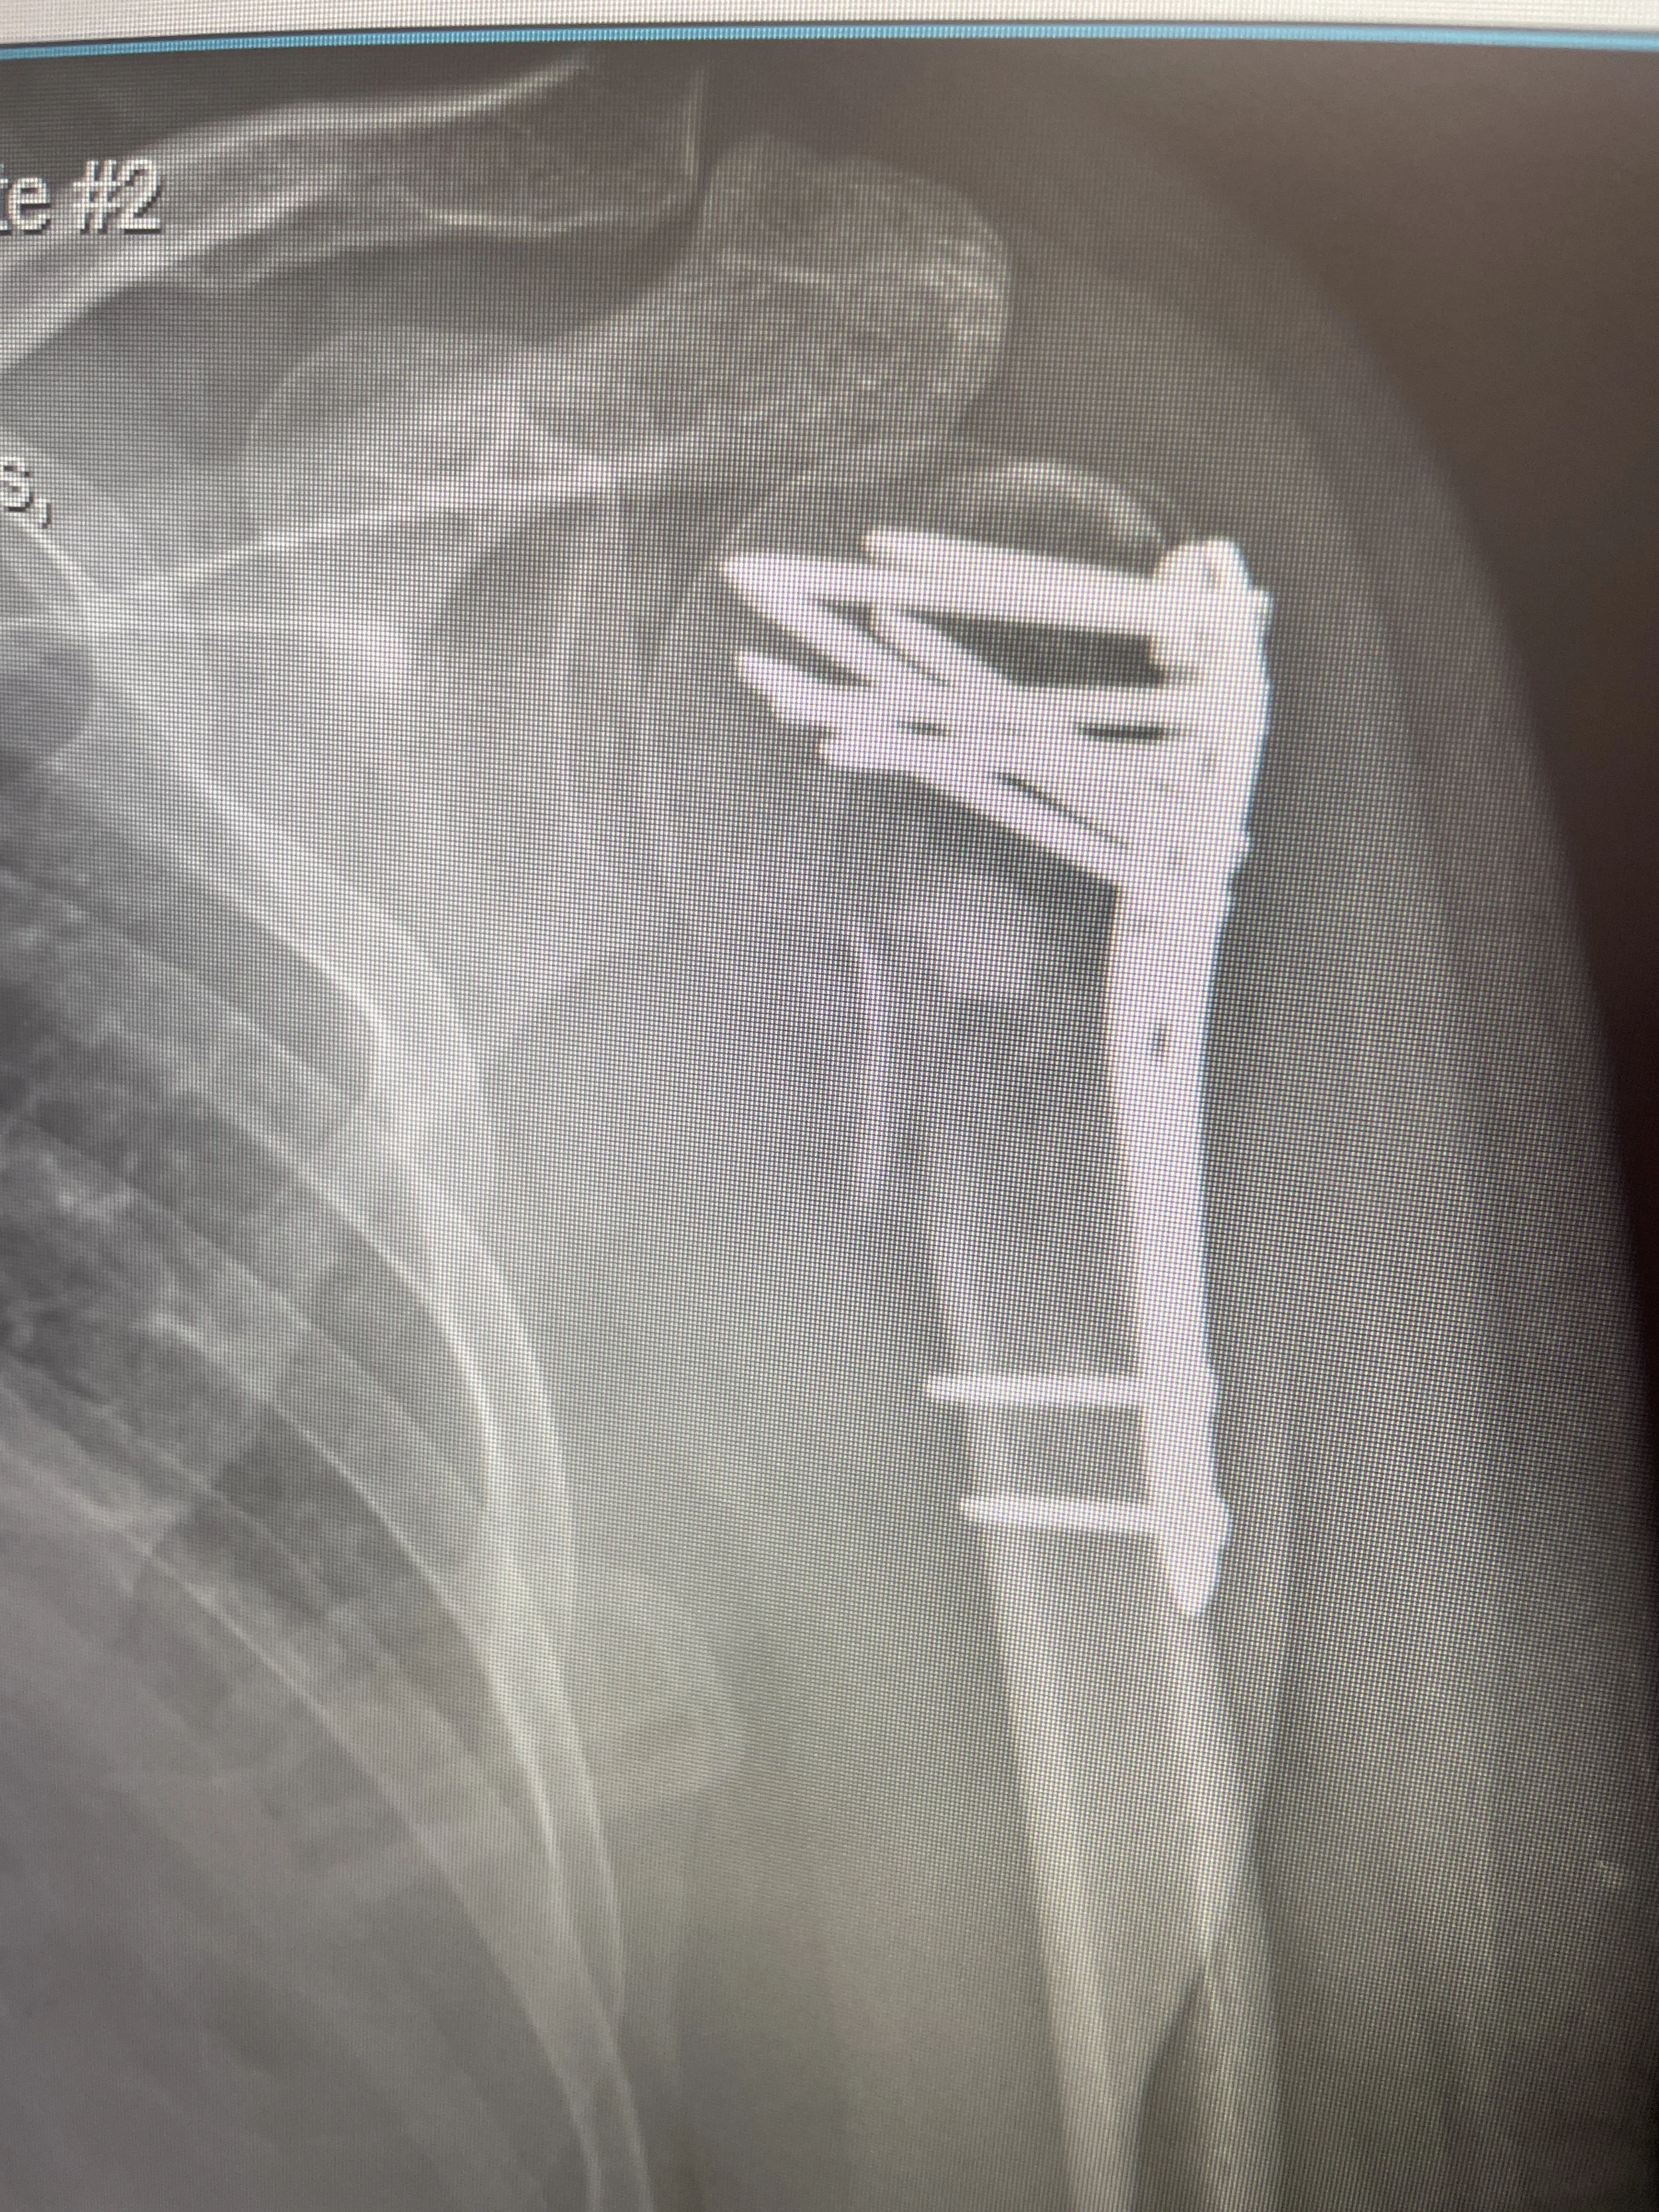

On today’s raw and unfiltered episode of In Love with the Process, host Mike Pecci pulls back the curtain on life post-accident. From confronting his fear of the dark spiral of opioid addiction to navigating the emotional landmines of recovery, Mike opens up about how a shattered shoulder reshaped his outlook on pain, purpose, and partnership. It’s an honest, gritty check-in about finding strength in vulnerability, leaning on the people who show up when it really counts, and turning setbacks into fuel.